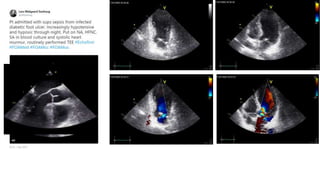

January 9th, 2015

August 6th,

2016

Circulation. 2017;136:2178–2188